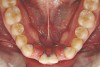

Figure 5e  Anchorage plate was stabilized to piriform rim (E through H). Final result 12 months postsurgery (F). There is significant lateral dentoalveolar expansion of arches and alveoloskeletal correction in maxillary and mandibular anterior regions. Alveolar bone volume was increased in lower anterior to create optimal implant sites and establish ideal interincisal function and stability.

Figure 5e

Figure 5f  Anchorage plate was stabilized to piriform rim (E through H). Final result 12 months postsurgery (F). There is significant lateral dentoalveolar expansion of arches and alveoloskeletal correction in maxillary and mandibular anterior regions. Alveolar bone volume was increased in lower anterior to create optimal implant sites and establish ideal interincisal function and stability.

Figure 5f

Figure 5h  Final facial views show significant esthetic enhancements with broader maxillary arch, correction of “gummy smile,” and fuller lip support (I and J). Restorative dentist: John L. Garlinghouse, DMD.

Figure 5h

Figure 5i  Final facial views show significant esthetic enhancements with broader maxillary arch, correction of “gummy smile,” and fuller lip support (I and J). Restorative dentist: John L. Garlinghouse, DMD.

Figure 5i